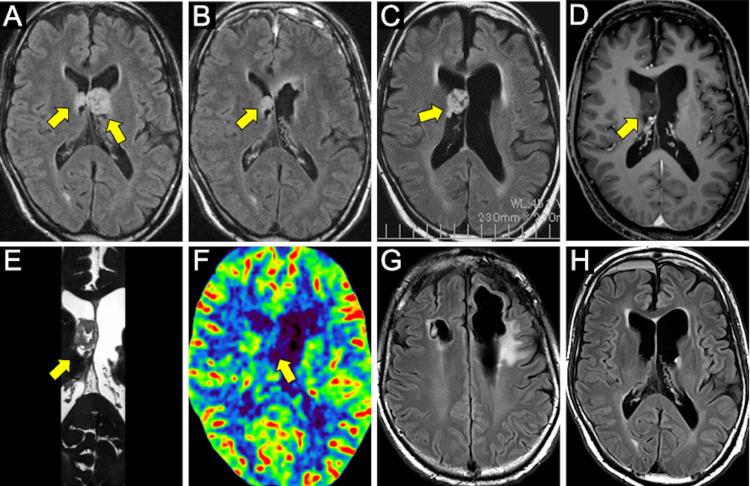

Subependymoma is a benign, slow-growing tumor that arises from the ventricular wall. Although often asymptomatic, it can obstruct cerebrospinal fluid flow, leading to hydrocephalus. Most subependymomas are unilateral, typically located in the fourth ventricle, followed by the lateral ventricles. Bilateral involvement of the lateral ventricles is extremely rare. We report the case of a 62-year-old man with bilateral subependymomas located in the anterior horns of both lateral ventricles, who presented with impaired consciousness due to epilepsy. Nineteen years earlier, the tumor in the anterior horn of the left lateral ventricle had been resected via craniotomy with frontal lobe uncapping. The lesion in the right lateral ventricle, initially small, gradually enlarged over two decades and was subsequently resected using flexible neuroendoscopy. This approach allowed safe and effective tumor removal within a spacious intraventricular working environment while maintaining minimal invasiveness. In cases involving relatively small and hypovascular intraventricular tumors, flexible neuroendoscopy represents a viable minimally invasive surgical option. Continued technological advancements are anticipated to further enhance the safety and applicability of neuroendoscopic tumor resections.

室管膜下瘤是一种起源于脑室壁的良性、生长缓慢的肿瘤。虽然通常无症状,但它可阻塞脑脊液流动,导致脑积水。大多数室管膜下瘤是单侧的,典型地位于第四脑室,其次是侧脑室。双侧侧脑室受累极为罕见。我们报告一例62岁男性,双侧室管膜下瘤位于双侧侧脑室前角,因癫痫发作导致意识障碍。19年前,左侧脑室前角的肿瘤已通过开颅额叶去骨瓣切除术切除。右侧脑室的病变最初较小,在二十年内逐渐增大,随后使用软性神经内镜切除。这种方法在宽敞的脑室内工作环境中实现了安全有效的肿瘤切除,同时保持了最小的侵袭性。对于涉及相对较小且血供不丰富的脑室内肿瘤的病例,软性神经内镜是一种可行的微创外科选择。预计技术的不断进步将进一步提高神经内镜肿瘤切除术的安全性和适用性。